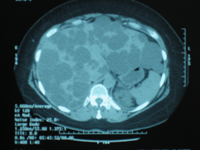

Polykystose hépatique